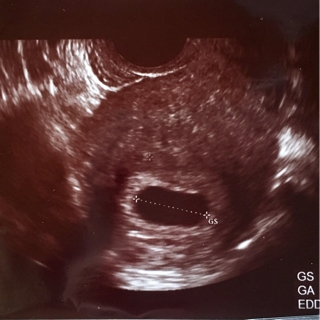

2回目…2月18日

胎嚢21.3mm

あれ胎嚢、小さくなってる…

形が横長になった気が…